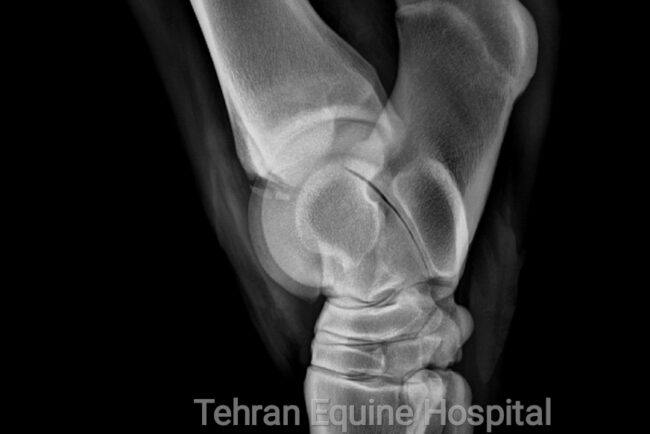

Subchondral bone Fragments in tarsal joint